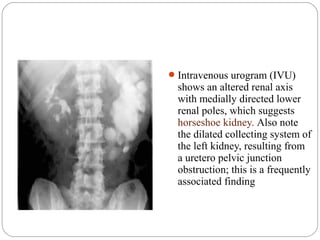

Intravenous urogram (IVU)

shows an altered renal axis

with medially directed lower

renal poles, which suggests

horseshoe kidney. Also note

the dilated collecting system of

the left kidney, resulting from

a uretero pelvic junction

obstruction; this is a frequently

associated finding